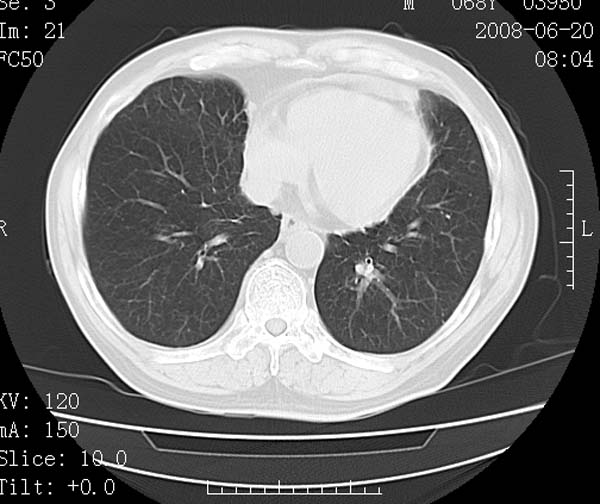

以下是引用守望可可西里在2008-6-24 1:11:00的发言:[br][br] 考虑为周围型肺癌:[br] 1.分叶结节,形态极不规则,蟹足样伸展的恶性浸润特征比较明确。[br] 2.磨玻璃影中由多个更高密度小结节聚集呈梅花瓣样。[br] 3.局部胸膜凹陷征比较明确。[br][br] 另:纵隔胸膜明显增厚、粘连。

以下是引用zjzjr在2008-6-24 11:19:00的发言:[br]支持左下肺周围型肺癌伴右肺转移,纵隔淋巴结转移,心包积液.

以下是引用zhangling在2008-6-24 14:56:00的发言:[br]我们科室意见报告为[br][br]1考虑左下肺周围型肺癌[br]2右肺小结节考虑转移瘤,纵隔淋巴结转移[br]3心包积液. [br] 各位老师分析的相当好 谢意[br]